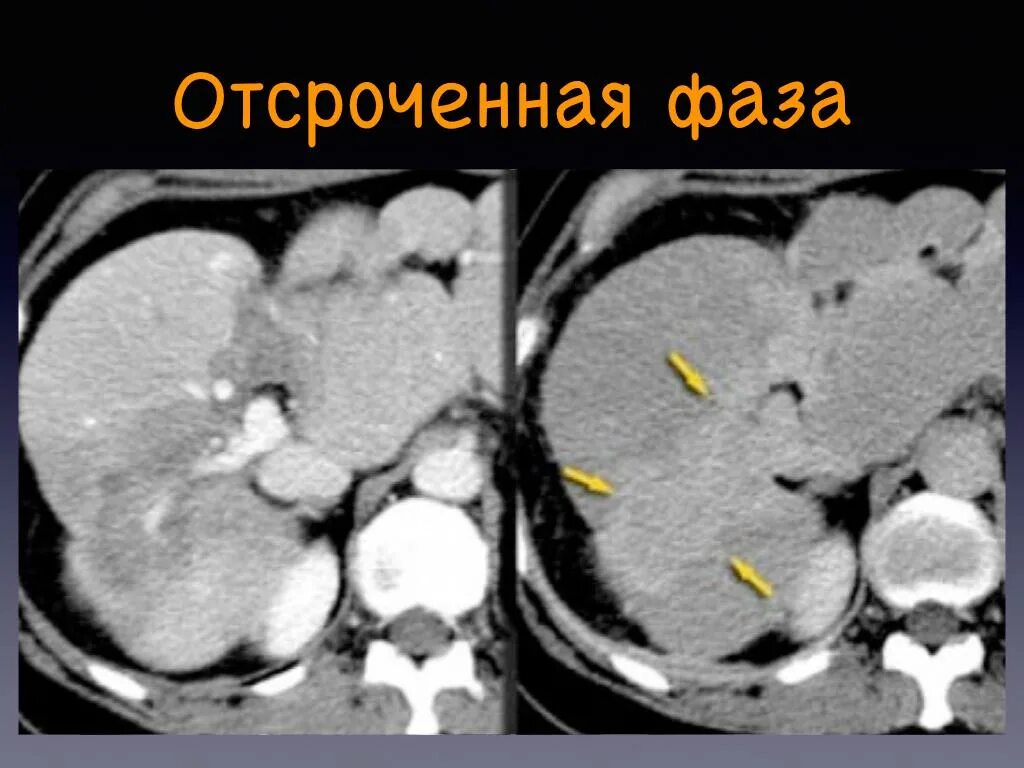

Фазы кт